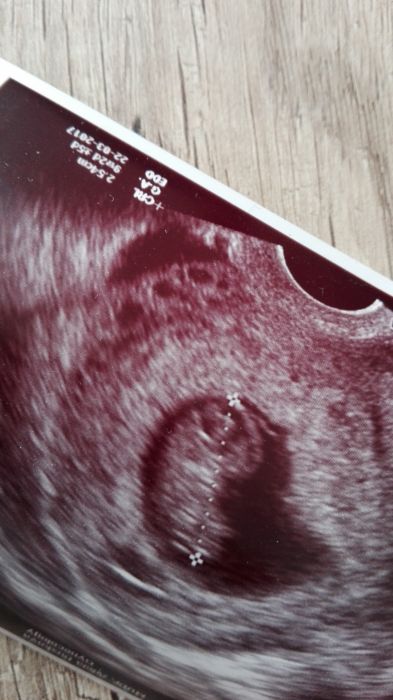

Co vidíte na ultrazvuku?